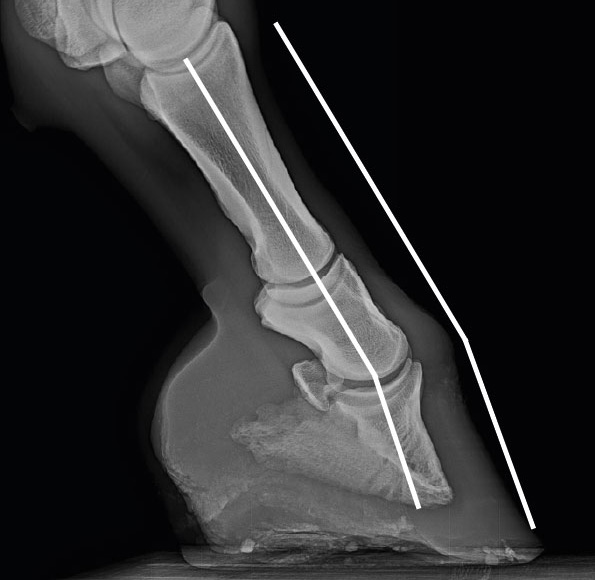

Eine Analyse von etlichen Röntgenaufnahmen zeigte eindrucksvoll, wie sich die Knochen der Knochensäule einer zur Seite verschobenen Belastung anpassen können. Die folgende Aufnahme zeigt beispielhaft anhand der weißen Linie, wie sehr zur Seite versetzt die Kräfte in den einseitigen Huf eingeleitet werden und wie sich die Knochen der Belastung angepasst haben.

Röntgenbild eines Vorderhufes von hinten (palmar) mit einer einseitigen Mehrbelastung, durch die sich die inneren Strukturen der verschobenen Belastung angepasst haben

Röntgenbild eines Vorderhufes von hinten (palmar) mit einer einseitigen Mehrbelastung, durch die sich die inneren Strukturen der verschobenen Belastung angepasst haben, sogar die Knochen der Knochensäule.

Röntgenbild eines Hufes mit nach hinten gebrochener Huf-Fessel-Achse und einer Überstreckung des Krongelenkes

Röntgenbild eines Hufes mit nach hinten gebrochener Huf-Fessel-Achse und einer Überstreckung des Krongelenkes.